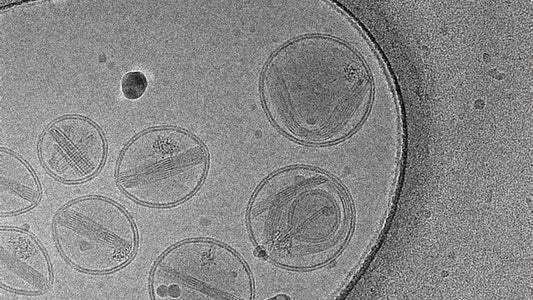

Lipid Nanoparticles and Their Link to TTS, GBS,...

Recent studies have raised concerns about the potential role of lipid nanoparticles (LNPs) in triggering immune-related conditions. Evidence suggests a possible connection between LNPs and thrombosis with thrombocytopenia syndrome (TTS),...